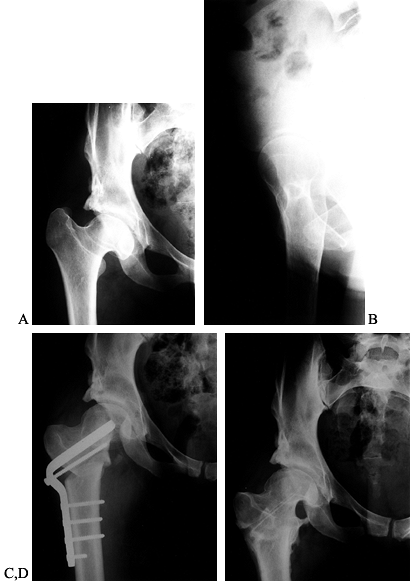

Figure 104.21. Revision of a previous, inadequate PAO. AP view of the left hip in a 31-year-old woman with dysplasia and pain (A). This AP view of the left hip shows an attempted periacetabular procedure done elsewhere (B). AP views of the hip (C) and pelvis (D)

over a year later show subluxation of the hip with poor coverage and the patient had increasing pain. A revision PAO was done. At 3 months after surgery, the patient was already walking without aids and limping only late in the day. At 8 months after surgery, it is healed (E,F). False profile view of the left hip preoperative before revision (G) and postoperative when healed (H). |

Figure 104.22. PAO salvage of a failed Chiari osteotomy. A: AP radiograph of the pelvis in a 37-year-old woman prior to Chiari osteotomy for the right hip done elsewhere. B: Postoperative radiograph after the Chiari procedure. C:

This radiograph of the pelvis is 4 years after a salvage PAO on the right. Patient had no pain and no limp on left but did have a Trendelenberg limp on right. D: This false-profile view of the right hip is just prior to salvage PAO. E: A postoperative radiograph. |